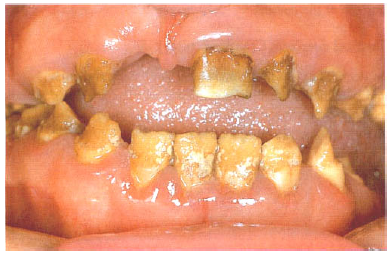

Enamel matrix is formed in normal quantity but poorly calcified. When newly erupted, the enamel is normal in thickness and form, but weak and opaque or chalky in appearance.The teeth tend to become stained and relatively rapidly worn away. The upper incisors may acquire a shouldered form due to the chipping away of the thin, soft enamel of the incisal edge (Fig. 5). There are dominant and recessive patterns of inheritance.

![]() | |

| Figure 5. Amelogenesis imperfecta, hypocalcified type. The soft chalky enamel was virtually of normal thickness and form but has chipped away during mastication. |